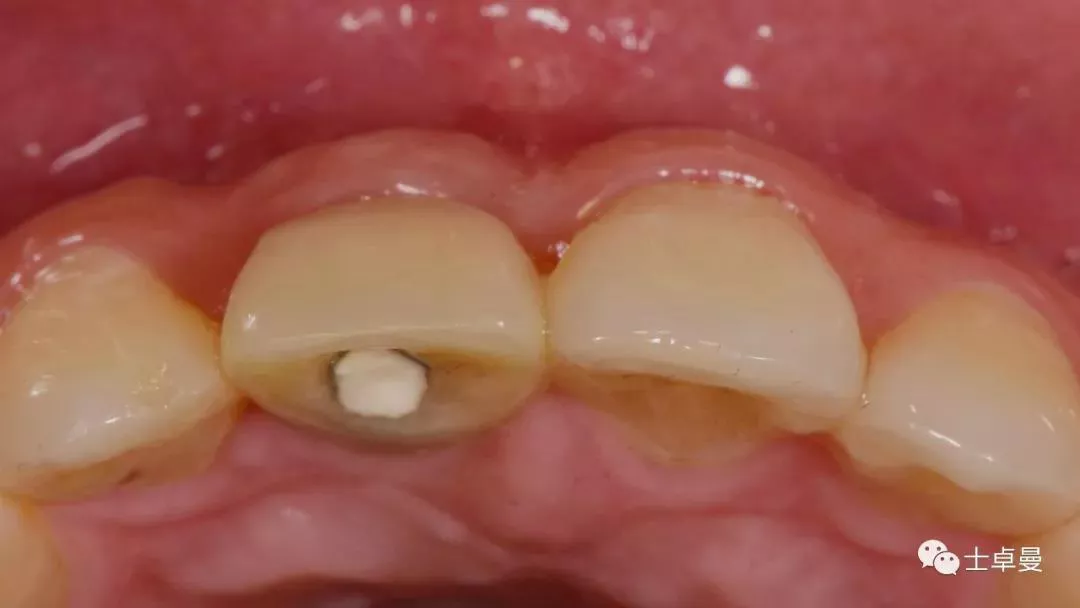

口内检查

· 11牙冠折断,余留残根;

· 唇侧位于龈上2mm,腭侧达骨下1mm,根管内封药存;

· 探(-),冷 (无反应),叩 (-),松 (-),牙龈可;

· 中位笑线,牙龈生物型为中弧形、中厚龈生物型;